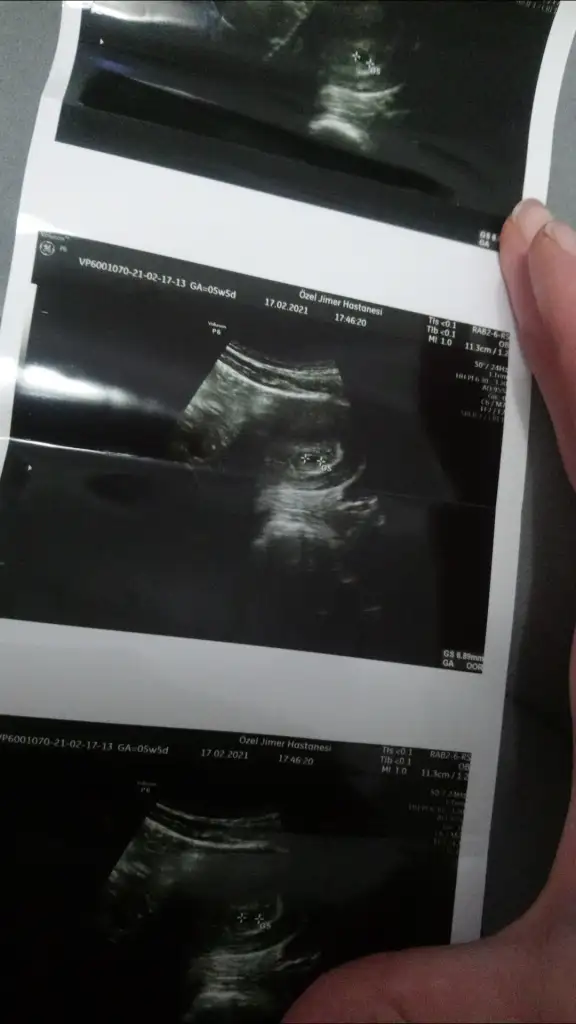

Canim benim ikizlere de tahminde bulunur musun? 8+4, 8+6ken vajinal ultrason goruntuleri. Benim için cinsiyet onemj yok ama biliyorsaniz denemek istedim ben de

Eklentiler

• 20210323_183359.webp

35,4 KB · Görüntüleme: 123